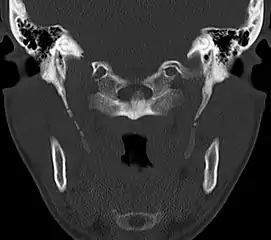

CT scan, coronal section showing bilateral extended styloid process and stylohyoid ligament ossification (incidental finding)

Imaging is important and is diagnostic. Visualizing the styloid process on a CT scan with 3D reconstruction is the suggested imaging technique.[12] The enlarged styloid may be visible on an orthopantogram or a lateral soft tissue X ray of the neck.